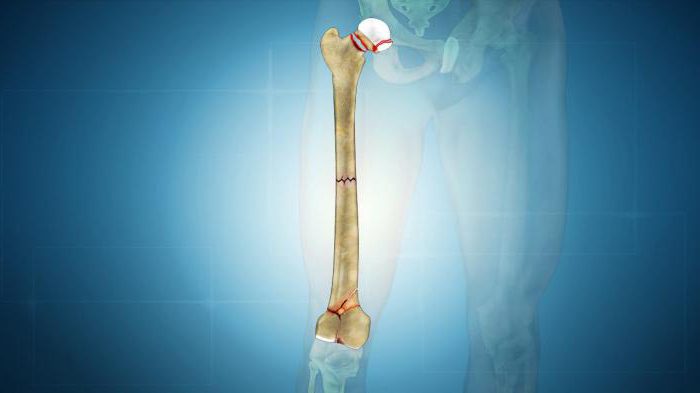

Различают целый ряд патологических переломов бедренной кости. Их классификация отображает общую классификацию таких повреждений. В зависимости от локализации линии перелома бывают патологические переломы:

- тазобедренного сустава;

- шейки бедра;

- диафиза;

- мыщелковые.

Диафизарным патологическим переломом бедренной кости является нарушение целостности диафиза – той части, которая находится между двумя эпифизами (концами кости). Такие переломы наиболее часто сопровождаются смещением костных фрагментов. Если возникла травматизация верхней трети кости, то под воздействием ягодичных мышц отломки смещаются в разные стороны, при повреждении в нижней трети бедренной кости икроножная мышца тянет костные фрагменты в заднем направлении.

Мыщелковые патологические переломы бедренной кости также диагностируются несколько реже. Их выявляют в нижнем сегменте бедренной кости, который принимает участие в формировании коленного сустава.